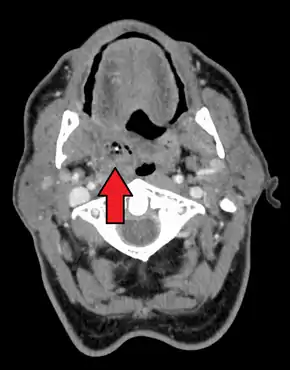

![]() | |

| Right sided peritonsillar abscess | |